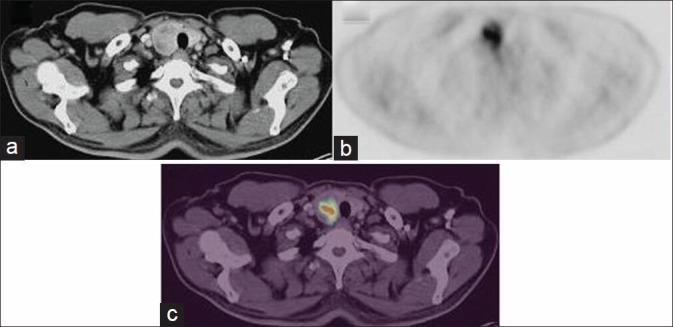

Differentiated thyroid cancer frequently metastasizes but generally spreads to regional cervical lymph nodes and, in advanced cases, to the lungs and/or skeleton. Metastases to the skin/subcutaneous tissue are rare. We report 45-year-old male patient presented with a loin swelling which on biopsy showed a papillary carcinoma and referred for fluorodeoxyglucose-positron emission tomography/computed tomography (FDG PET/CT) to find out the primary disease. PET/CT showed abnormal FDG uptake within a loin metastasis and right lobe thyroid nodule. Fine-needle aspiration from nodule showed papillary carcinoma. Because thyroid cancer can rarely metastasize to the skin, attention should be given to that region during interpretation of the images. He was advised total thyroidectomy and metastasis excision.